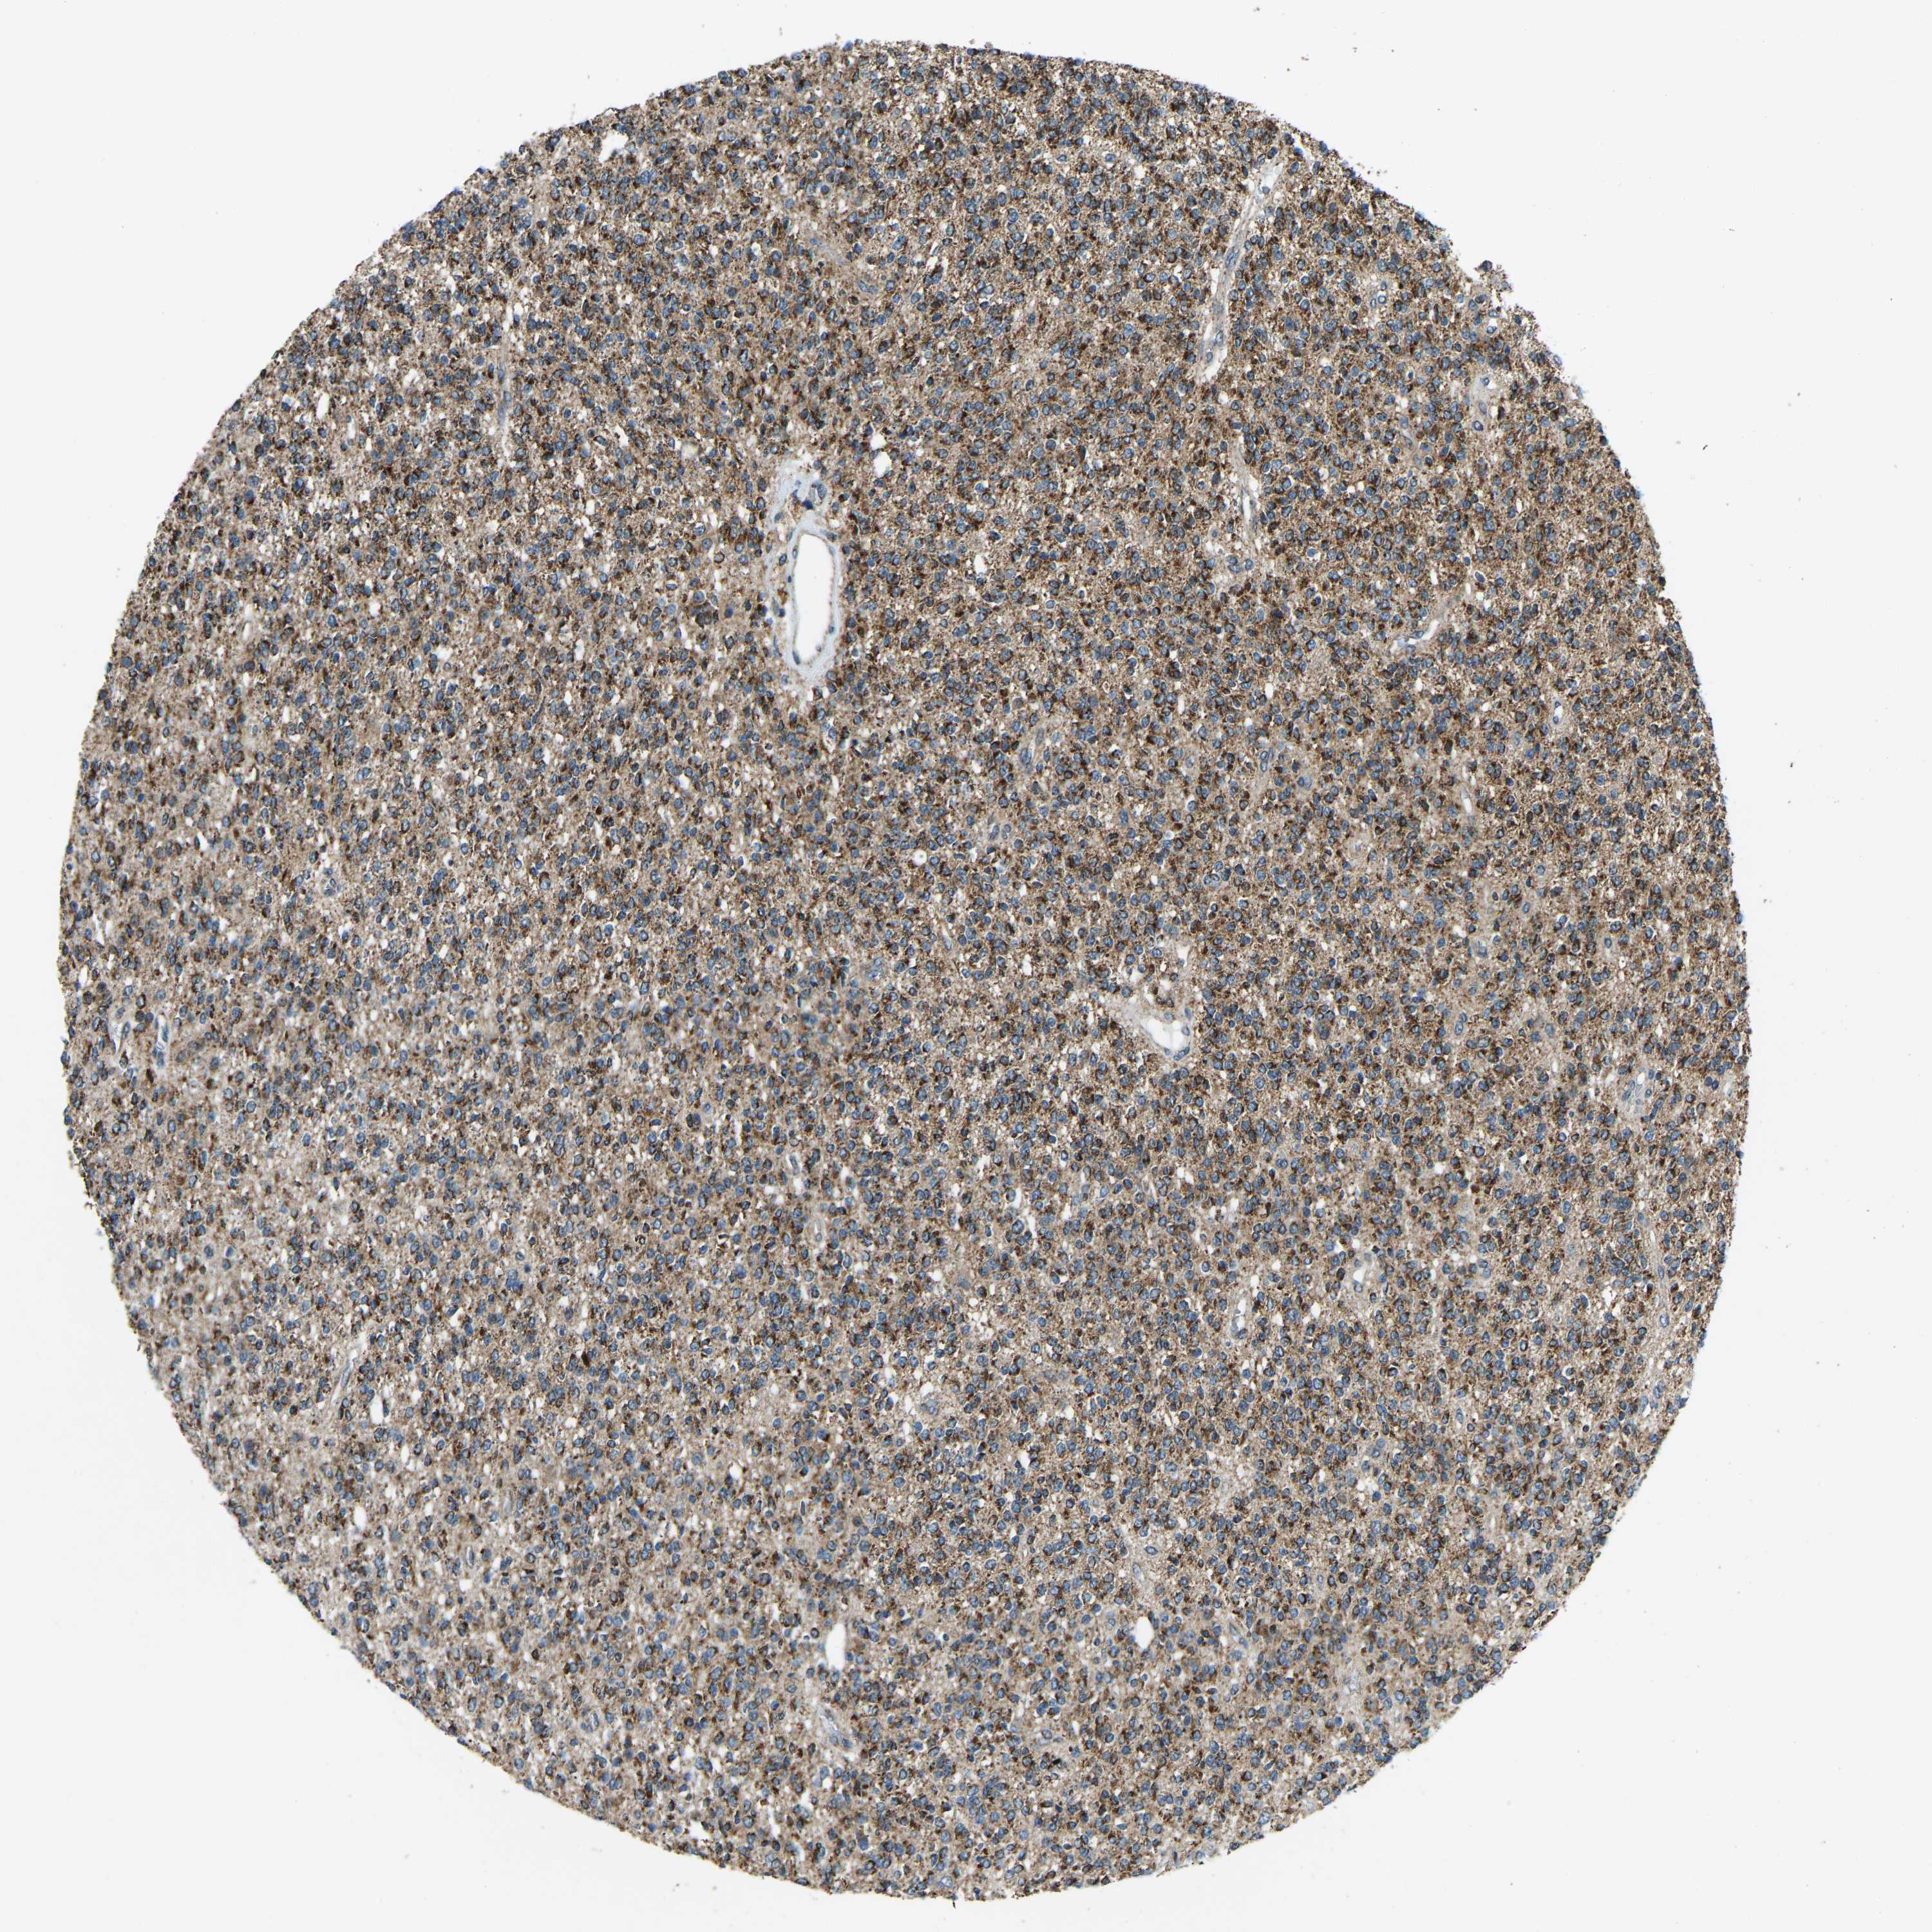

GLIOMA - Protein expressioni

A mouse-over function shows sample information and annotation data. Click on an image to view it in a full screen mode. Samples can be filtered based on level of antibody staining by selecting one or several of the following categories: high, medium, low and not detected. The assay and annotation is described here.

Note that samples used for immunohistochemistry by the Human Protein Atlas do not correspond to samples in the TCGA dataset.

Antibody stainingi

Antibody staining in the annotated cell types in the current human tissue is reported as not detected, low, medium, or high, based on conventional immunohistochemistry profiling in selected tissues. This score is based on the combination of the staining intensity and fraction of stained cells.

Each image is clickable and will lead to virtual microscopy that enables deeper exploration of all samples and also displays staining intensity scores, fraction scores and subcellular localization as well as patient and tissue information for each sample.

Antibody HPA019232

Antibody HPA021497

Antibody HPA021768

Staining

High

Medium

Low

Not detected

Intensity

Strong

Moderate

Weak

Negative

Quantity

>75%

75%-25%

<25%

None

Glioma, malignant, High grade

Glioma, malignant, Low grade